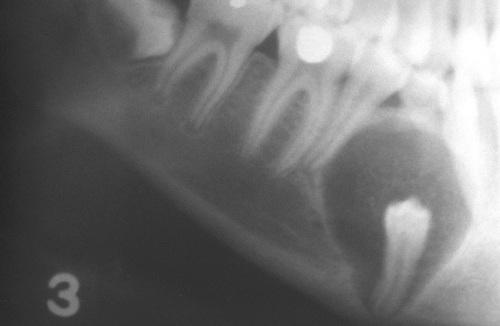

This large, multilocular cyst involves most of the ascending ramus and is growing in an anteroposterior direction.

odontogenic keratocyst (OKC)

This cyst involves the crown of an unerupted premolar, which appears similar to a dentigerous cyst.